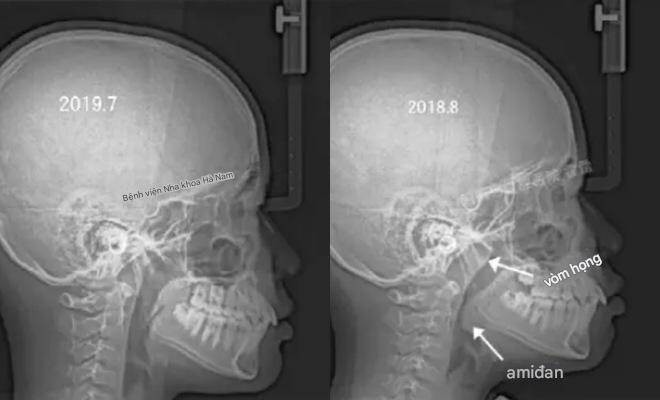

Trước đây, Giám đốc Zhang của Khoa Chỉnh nha thuộc Trường Nha khoa, Đại học Trịnh Châu, đã đăng một loạt ảnh lên Weibo:

Gia đình đưa cậu bé 11 tuổi đến khám vì miệng nhô ra bất thường.

Sau khi hỏi kỹ tiền sử, bác sĩ phát hiện cậu bé có thói quen ngủ há miệng vào ban đêm.

Kết quả chụp X-quang cho thấy đường thở mũi của cậu bị tắc nghẽn nghiêm trọng.

Đây chính là nguyên nhân khiến khuôn mặt cậu dần thay đổi.

Theo lời khuyên của bác sĩ, cậu bé đã được phẫu thuật cắt amidan và nạo VA. Một năm sau, trong lần khám theo dõi, tình trạng "miệng nhô" của cậu bé đã dần biến mất.